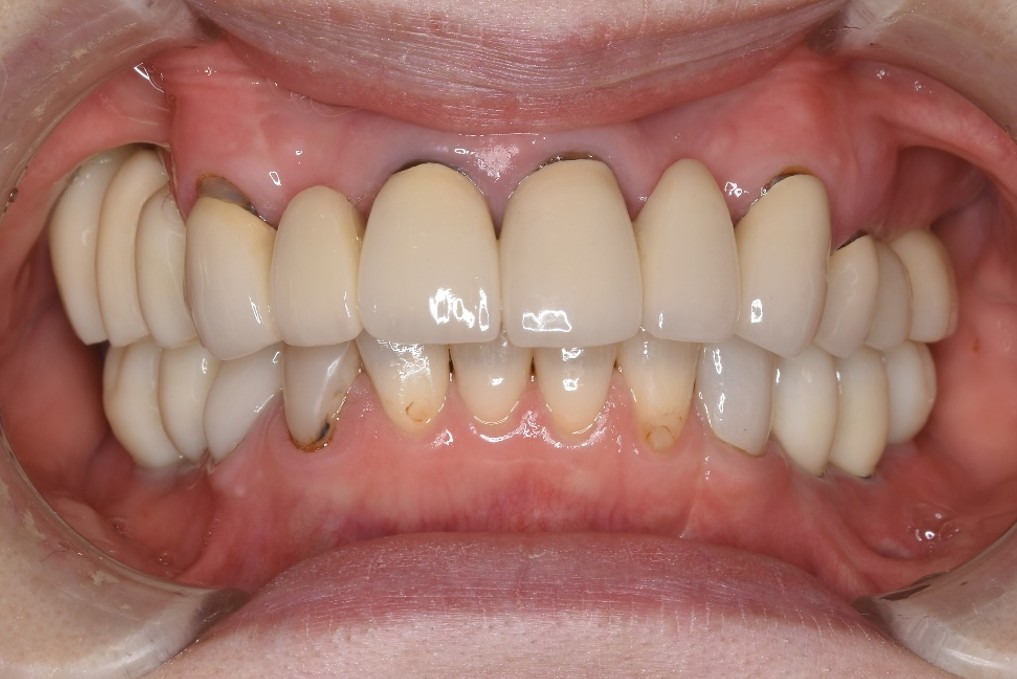

治療前

-

治療後